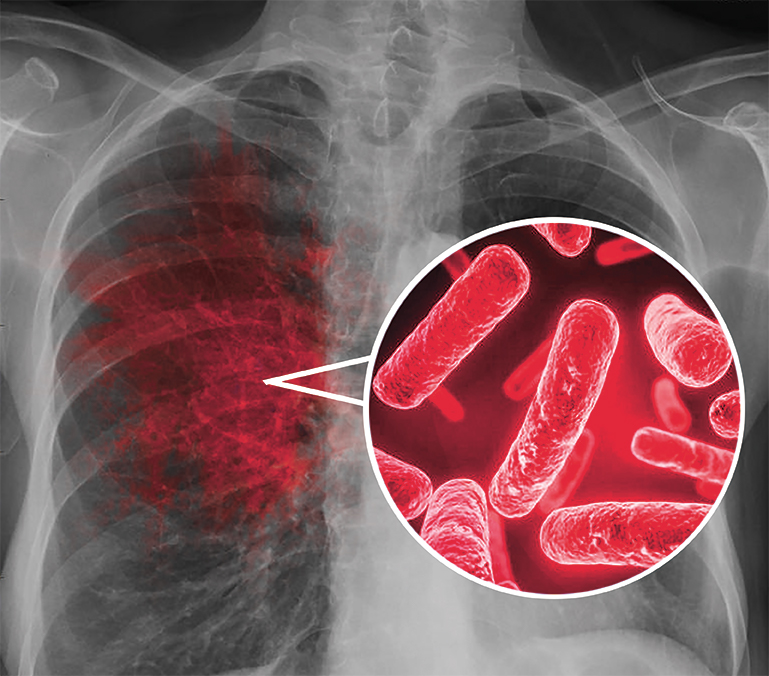

Симптомы и признаки туберкулеза: как распознать заболевание